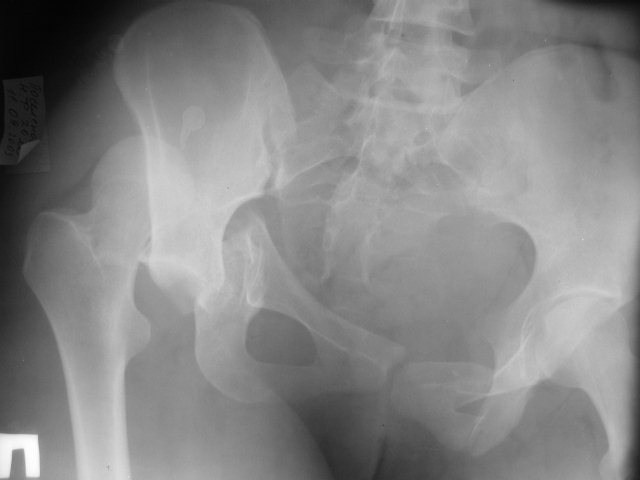

Больная 20 лет поступила в институт через 4 недели после травмы. Диагноз: Застарелый вывих правого бедра, поперечный перелом и перелом заднего края правой вертлужной впадины.

У больной имеется высокий поперечный перелом вертлужной впадины с подвздошным вывихом бедра, скорее всего на операции выявится небольшой дефект задней стенки, но необязательно.

Заключение зав.кафедрой травматологии-ортопедии ДВГМУ В.С.Яковлева:

Помимо застарелого вывиха бедра у больной определяется перелом крестца и разрыв правого крестцово-подвздошного сочленения, трансацетабулярный перелом таза, разрыв симфиза и перелом лонной и седалищных костей слева.